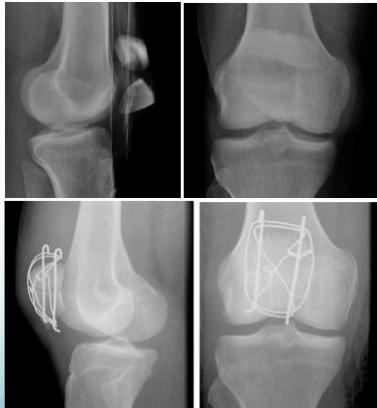

| Tension-band Wires | Indications: Patellar and olecranon fractures, possible in malleolar fractures. Application involves K-wires as a base. | , , , , ![]() |